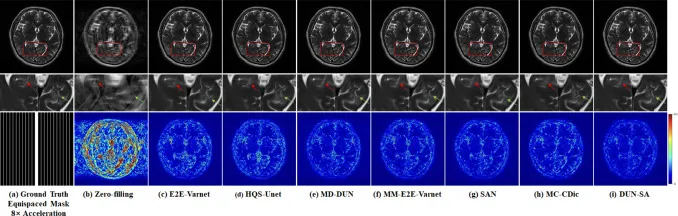

图4. 在fastMRI数据集上,1D等距欠采样掩模下4倍加速的代表性方法视觉比较。第一行:不同方法重建的图像;第二行:感兴趣区域的放大视图;第三行:4倍加速的等距掩模和不同方法的误差图。

图5. 在IXI数据集上,1D等距欠采样掩模下8倍加速的代表性方法视觉比较。第一行:不同方法重建的图像;第二行:感兴趣区域的放大视图;第三行:8倍加速的等距掩模和不同方法的误差图。